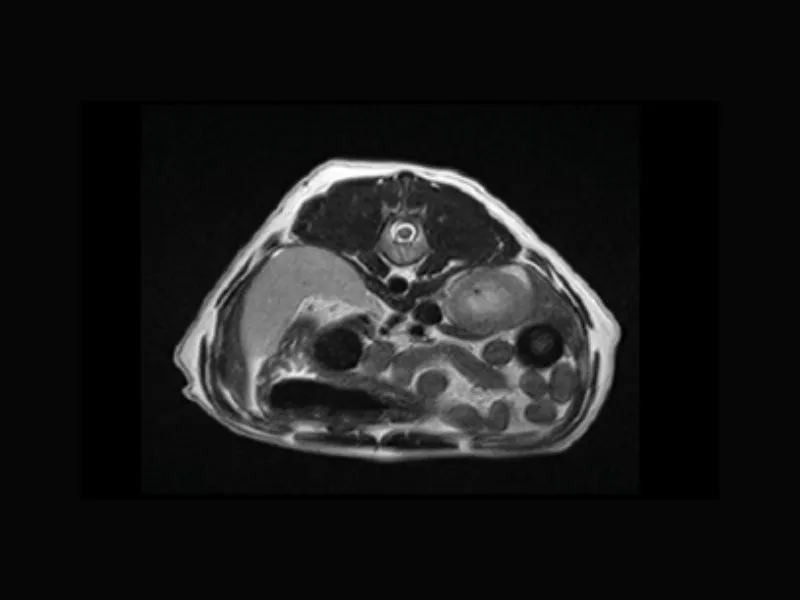

Clinical images

Small animals